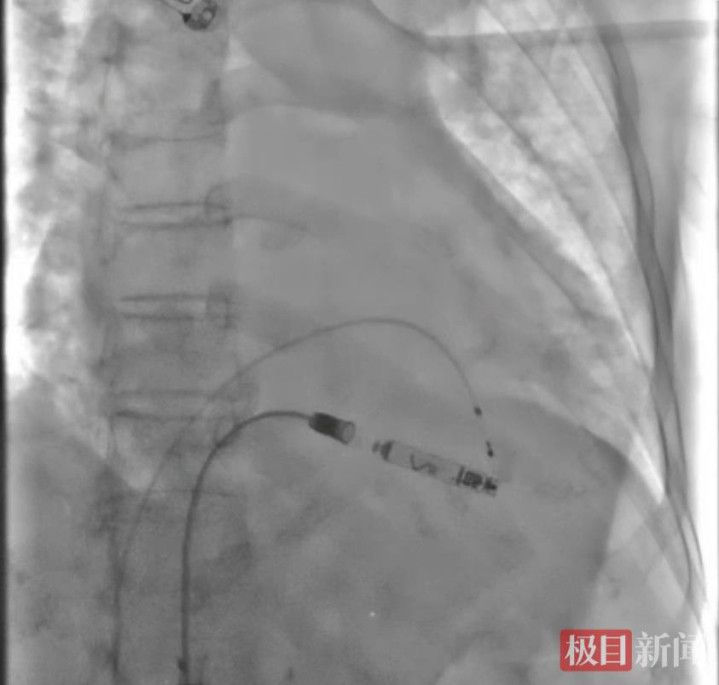

主动型无导线起搏器测试良好后释放